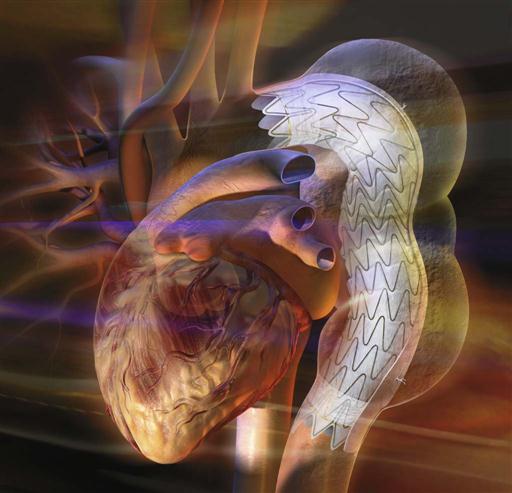

Endovascular, expandable stented tube grafts are available for both the abdominal aorta and the descending portion of the thoracic aorta (Figure 25-21). The endovascular graft is inserted percutaneously into the femoral artery and advanced to the desired position in the abdominal or descending thoracic aorta, where the prosthesis is opened, implanted, and secured (Thompson and Bertling, 2009; Tinkham, 2009).